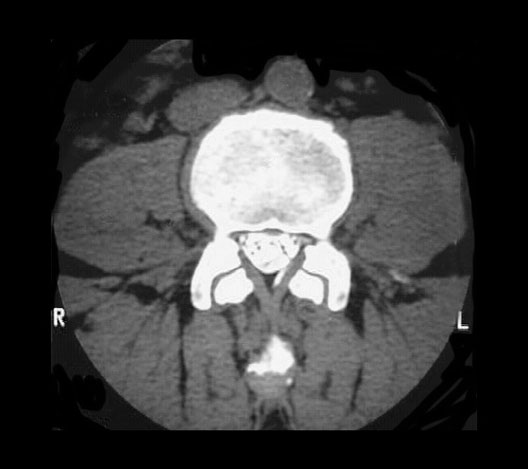

L3 CT After Myelography

Roll mouse over image to display labels.

1. Inferior Vena Cava

2. Aorta

3. Vertebral Body

4. Facet joint

5. Nerve rootlets of cauda equina

6. Inferior articular process

7. Superior articular process

8. Psoas Major Muscle